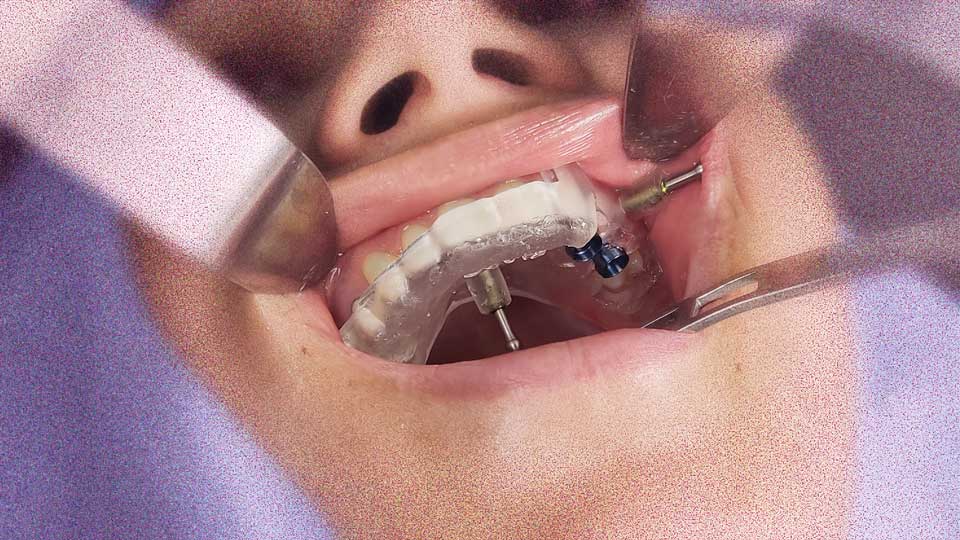

Implante Sem Cortes (Cirurgia Guiada por Computador)

Utilizamos tecnologia digital para planejar a cirurgia no computador antes mesmo de tocar no paciente. Isso permite a instalação dos implantes sem a necessidade de cortes com bisturi ou pontos, resultando em um pós-operatório sem dor, sem inchaço e com recuperação imediata.